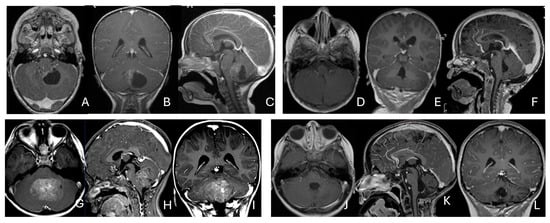

Objectives: Atypical teratoid/rhabdoid tumors (ATRTs) are rare, malignant central nervous system (CNS) neoplasms that predominantly affect infants and young children. While ATRT arises throughout the CNS, its extracranial counterpart, malignant rhabdoid tumor, occurs in other organs. A single-institutional cohort is reviewed to map

Objectives: Atypical teratoid/rhabdoid tumors (ATRTs) are rare, malignant central nervous system (CNS) neoplasms that predominantly affect infants and young children. While ATRT arises throughout the CNS, its extracranial counterpart, malignant rhabdoid tumor, occurs in other organs. A single-institutional cohort is reviewed to map anatomic distribution of pediatric ATRTs and to integrate a literature review to contextualize ATRT histogenesis from anatomical and embryological perspectives. Methods: A retrospective review was conducted on a cohort of 50 pediatric patients with ATRT treated over 20 years. Demographic, surgical, and neuroimaging data were correlated to define tumor location, extent, and compartmental involvement. A focused literature review synthesized molecular subclassifications and proposed cells of origin/cytogenesis. Results: Of the 50 ATRTs, 18 (36%) were infratentorial, 15 (30%) supratentorial, 11 (22%) in the pineal region, and 6 (12%) in the spinal compartment. Among infratentorial tumors, 10 were centered in the fourth ventricle, with or without extension into the cerebellopontine angle (CPA) cistern; the remainder arose in the CPA. Among ATRTs of the cerebral hemispheres, 3 showed bi-hemispheric involvement crossing the falx cerebri. ATRTs of the pineal region predominantly originated from the superior medullary velum. These topographic data were corelated with embryological and molecular information available in the literature. Conclusions: ATRTs arise across diverse neuroanatomical compartments—including intraparenchymal, intraventricular, extra-axial, and extradural sites—underscoring biological heterogeneity. Inactivation of SMARCB1 is the defining molecular event and principal oncogenic driver, although the upstream mechanisms precipitating these alterations remain incompletely resolved. Molecular subgroups—ATRT-TYR, ATRT-SHH, and ATRT-MYC—display distinct age distributions and anatomic predilections, implicating developmental context in tumor initiation. The characteristic cellular admixture of rhabdoid cells with mesenchymal and/or epithelial differentiation, together with intra- and extra-axial and occasional extradural presentations, supports a model in which at least a subset of ATRTs may originate from neural crest-derived lineages, despite little or no neural crest contribution to brain parenchyma development. Neural plate border progenitors with bipotent features represent a plausible intraparenchymal cell of origin. Definitive resolution of these origins and the mechanisms of SMARCB1 disruption will require integrated approaches. Further investigations are warranted to clarify these mechanisms.